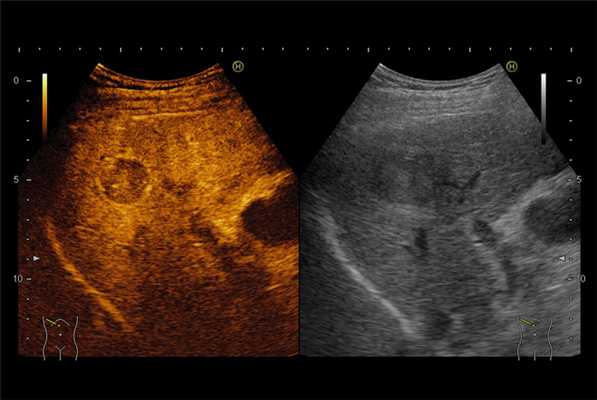

Улучшение отображения кровотока органа в режиме серой шкалы может способствовать обнаружению образований и дифференциации нормальных и патологических областей с использованием многих из тех критериев, которые уже рутинно используются в КТ и МРТ. На рисунке пример улучшенного обнаружения образования в печени, которое стало возможным благодаря импульсной инверсной гармонической визуализации (специальный режим УЗ изображения, применяемый при исследовании с контрастом).

Интермиттирующая гармоническая визуализация с контрастированием обеспечивает улучшение качества изображения всей ткани в капиллярной фазе, что позволяет увидеть аномалии перфузии. Американские ученые продемонстрировали, что интермиттирующая гармоническая визуализация эффективна для дифференциации доброкачественных и злокачественных заболеваний простаты.